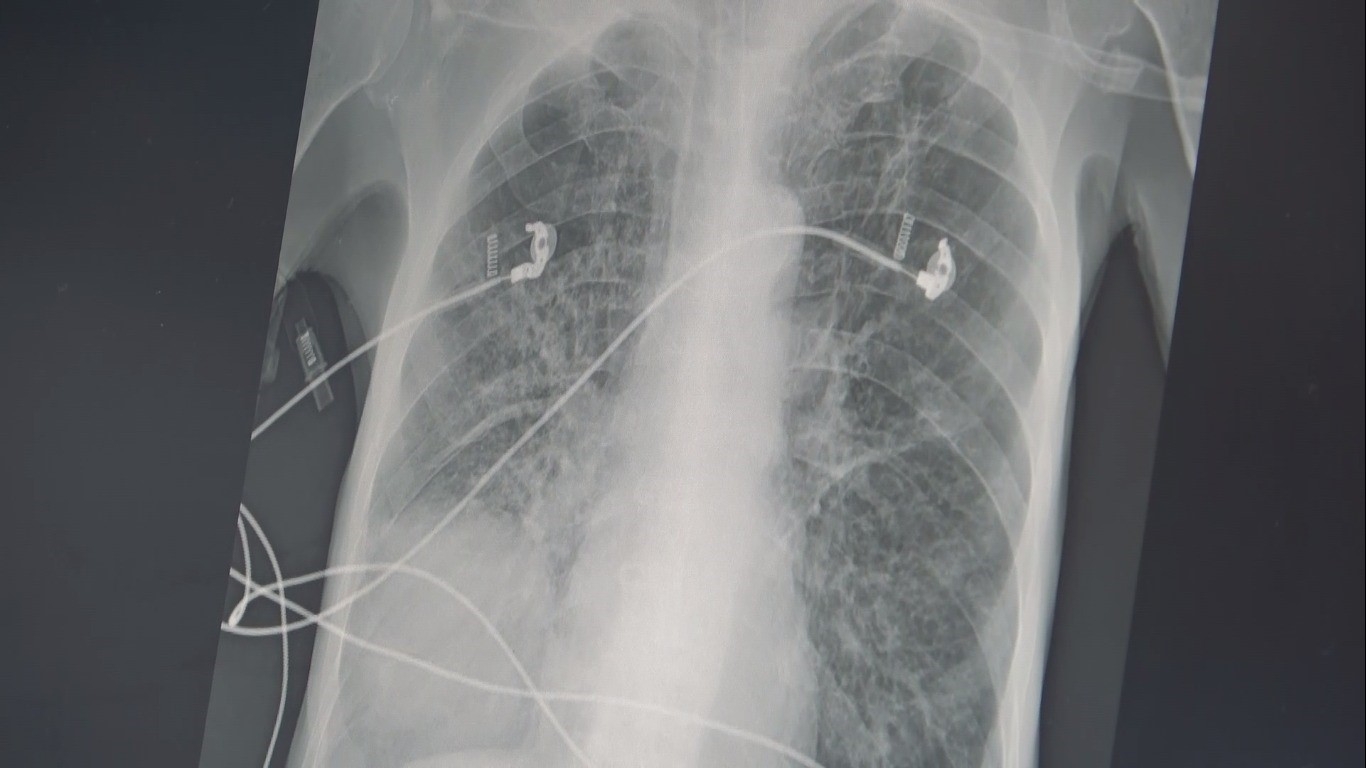

Göğüs Hastalıkları Uzm. Prof. Dr. Şevket Özkaya, "İçtiğiniz sigara 2 ölümcül hastalığın yüzde 90 sebebidir. Biri KOAH, diğeri akciğer kanseridir. Sigara içerseniz, kesecik duvarlarınızdaki elastik doku harap olur ve esneme yeteneğini kaybederek tıpkı bu naylon poşet gibi olur. 20 yıldan sigara kullanıyorsunuz bu iki hastalık ile her an yüzleşebilirsiniz" dedi.Sigara kullanımın zararlarının insanlara anlatmanın artık etkili olmadığını ifade eden Göğüs Hastalıkları Uzm. Prof. Dr. Şevket Özkaya, balon örneği üzerinde sigaranın verdiği zararı anlattı. Sigara kullanımın ortaokul yaşına kadar düştüğünü söyleyen Prof. Dr. Özkaya, "Ülkemizde 20 yaş üstündeki kişilerin en az yarısı sigara bağımlısıdır ve sigaraya başlama yaşı artık ortaokul çağlarına kadar indi. Sigaranın zararları anlatmak artık insanlarımızı etkilemiyor ama içtiğiniz sigara 2 ölümcül hastalığın yüzde 90 sebebidir. Bunlarda biri KOAH, diğeri ise akciğer kanseridir. Eğer yaşınız 40 üzeri ve içtiğiniz sigara paketi ile kullandığınız yılı çarpar, 20 paket/ yıldan daha fazla ise bu iki hastalık ile her an yüzleşebilirsiniz. KOAH teşhisi alan kişilerin büyük çoğunluğu halen sigara içen veya çok uzun süre sigara içmiş ve bırakmış kişilerdir. Hastalık sinsi ilerlediği için ve sigara bağımlıları öksürük, balgam çıkarma gibi şikayetleri önemsemedikleri için KOAH teşhisi konduğu zaman hastalar akciğer kapasitelerinin önemli bir kısmını kaybetmiş olmaktadırlar" diye konuştu."Peki sigara nasıl KOAH yapıyor"Akciğer keseciklerinin tıpkı bir balon gibi olduğuna dikkat çeken Özkaya, "Temiz havayı nefes olarak bu keseciklere aldığınızda şişer ve hava ile dolunca elastik yapısından dolayı içerdeki kirli havayı da tıpkı balonun sönmesi gibi dışarı atar. Bu mekanizma hayat kurtarıcıdır. Ancak sigara içerseniz, kesecik duvarlarınızdaki elastik doku harap olur ve esneme yeteneğini kaybederek tıpkı bu naylon poşet gibi olur ve nefes alırsınız ama balonun elastik yapısı olmadığı için kirli havayı dışarı atamazsınız ve içerde kirli hava kalır. Siz yeni bir temiz havayı nefes le almak istediğinizde keseciklerde temiz havanın gireceği yer kalmayacak ve nefes alamama yani nefes darlığı başlayacak" şeklinde konuştu."Her hücre kanserden ölecek"Kişilerin uzun yaşama imkanı da olsa her hücrenin kanserden öleceğini belirten Özkaya, "Sigaranın diğer ölümcül sebebi ise akciğer kanseridir. Biz şunu biliyoruz ki, yaşayan her sağlıklı hücrenin sonu kanser. Eğer diğer hastalıklar, kazalar ve erken ölümler olmasa ve uzun yaşama imkanı olsa her hücre kanserden ölecek. Eğer sigara kullanıyor veya kanserojen maddelere maruz kalıyorsanız, bu kansere yakalanma yaşınızı düşüren bir faktör. Örneğin; 150 veya 170 yaşında akciğer kanseri olacak bir kişi, sigara içtiği için bu yaş 100'e düşüyor. Eğer ailede kanser öyküsü varsa bu yaş daha da düşüyor. Ve 45 yaşından sonra her an kanser gelişmesi ile karşı karşıya kalınıyor. Sigara içmeye hiç başlamayarak bu iki ölümcül nefesten kurtulabilir ya da bırakarak bu iki ölümcül hastalık riskinizi azaltabilirsiniz" şeklinde konuştu. İHA